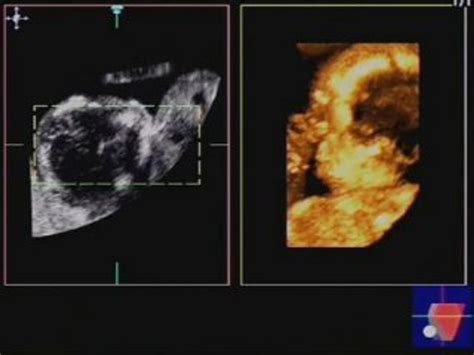

La gravidanza gemellare, come abbiamo detto, deve essere seguita da un ginecologo specializzato ed esperto, soprattutto per l’esecuzione delle ecografie. La diagnosi di zigosità, corionicità e amnionicità è fondamentale, poiché la differenza in termini prognostici dei vari tipi di gemellarità cambia in maniera sostanziale. L’ecografia del I trimestre è di fondamentale importanza e permette di stabilire la corionicità (una o due placente), l'amnionicità (uno o due sacchi), l'epoca gestazionale attraverso la misurazione del CRL quando la misura è tra 45-85 mm, e la determinazione del labeling (posizione) fetale.

Questa diagnosi dipende da numerosi fattori: l'epoca di amenorrea (è più facile entro le 10 settimane; poi diventa sempre più difficile), l'apparecchiatura ecografica utilizzata (migliore è l’ecografo, più facile è la diagnosi), e il pannicolo adiposo materno (nelle donne obese la diagnosi è sempre più difficile). La diagnosi ecografica di corionicità raggiunge, in epoca adeguata, con apparecchiature avanzatissime e con pannicolo adiposo non esuberante, un’affidabilità del 95%. L’unico dato certo per una diagnosi di gravidanza gemellare è l’ecografia che, come ci dicono le linee guida, in assenza di complicanze la prima ecografia deve essere effettuata intorno all’undicesima-dodicesima settimana di gravidanza. A titolo informativo, la presenza dei gemelli si vede già intorno alla quinta-sesta settimana di gravidanza, quando, come nelle gravidanze singole, si palesa la gravidanza in utero attraverso la presenza della camera gestazionale con dentro un embrione e il sacco vitellino. La diagnosi di corionicità e di amnionicità della gravidanza gemellare, invece, è raccomandata prima della quattordicesima settimana, e più precisamente tra l’undicesima e la tredicesima.

Ad ogni controllo ecografico dovrebbero essere valutati: biometria fetale, liquido amniotico, doppler dell'arteria ombelicale, lunghezza della cervice. La discordanza nei parametri di crescita fetale (PFS) dovrebbe essere documentata in ogni controllo a partire dalle 20 settimane. Nelle monocoriali dovrebbero essere valutati la velocità sull’arteria cerebrale media e il liquido amniotico. In più nelle monocoriali andrebbe eseguito l’ecocardio fetale.